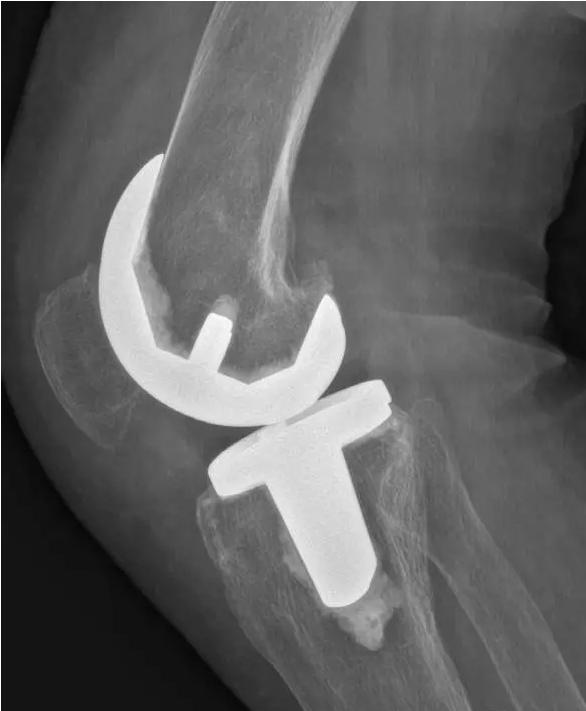

针对晚期(重度)骨关节炎,保守治疗无效时,要积极考虑手术治疗。目前效果最佳的手术方式即为关节置换手术,其他手术方式如关节融合手术等效果较关节置换术相差较大,已不在临床广泛使用。关节置换手术的目的是缓解患者疼痛,矫正关节畸形,恢复关节功能,恢复正常生活。针对老年人来说,积极的手术治疗可以有效恢复其日常生活,避免因疼痛及活动障碍导致患者扶拐或坐轮椅,有效减少因缺乏运动导致的心肺功能障碍及精神问题发生。经过几十年的发展,目前关节置换技术已十分成熟,临床上目前采用的微创技术,手术创伤小,术中出血非常少,术后第二天患者即可下地行走,三月之后即可恢复正常生活及功能。至于人工假体使用寿命,目前进口关节多为20-30年,能满足60-70岁患者的需求。需要关注的是,在行关节置换手术之后,患者仍需要进行积极的康复治疗,包括关节活动度及周围肌力的锻炼等,这样才能达到最佳的手术效果。

术后图如下: